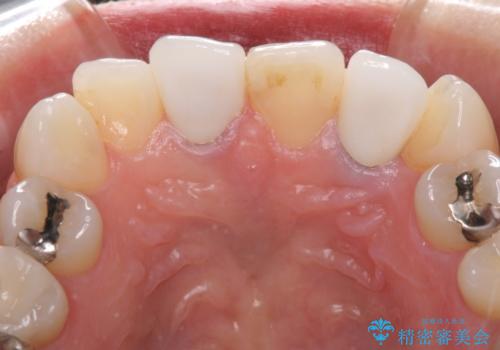

2歯をオールセラミッククラウン(ジルコニアクラウン)にて補綴することとしました。

土台の金属はグラスファイバーを含有したものに、クラウンの土台は強化セラミックとすることで、自然な前歯に仕上がりました。